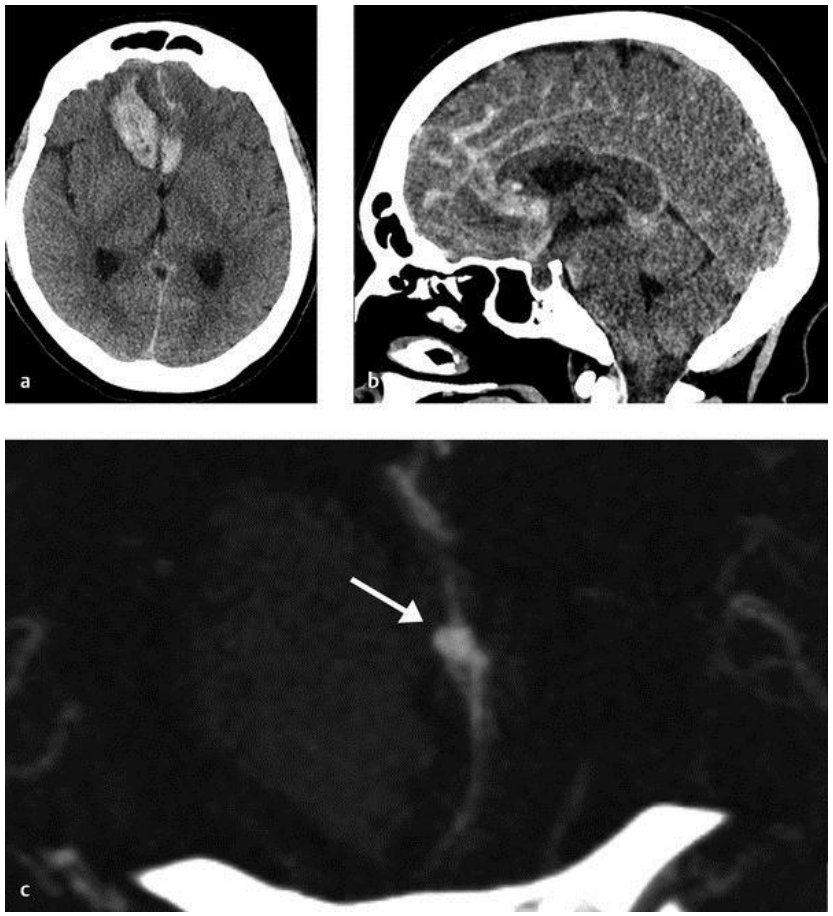

Một số nguyên nhân mạch máu gây xuất huyết não thường gặp trong thực hành lâm sàng bao gồm: phình động mạch não, dị dạng thông động tĩnh mạch não (AVM), dị dạng rò động tĩnh mạch màng cứng (dAVF), huyết khối xoang tĩnh mạch não.

Hình ảnh xuất huyết dưới nhện và trong nhu mô não do phình mạch não vỡ (hình mũi tên chỉ trên CT mạch).

Cộng hưởng từ (MRA) có độ nhạy để chẩn đoán xuất huyết não tương đương với CT sọ não không tiêm thuốc cản quang. MRA có thể phát hiện các nguyên nhân gây xuất huyết não như các u não chảy máu hay nhồi máu chuyển dạng chảy máu. Ở các bệnh nhân suy thận hay dị ứng thuốc cản quang thì việc đánh giá mạch não có thể thực hiện được thông qua MRA mạch máu mà không cần tiêm chất tương phản. Tuy nhiên, do giá thành cao, việc thăm khám kéo dài và tính khả dụng thấp hơn CT sọ não nên MRA ít khi được sử dụng để chẩn đoán xuất huyết não trong bệnh cảnh cấp cứu.

Hình ảnh xuất huyết não trên MRA có thể đặt ra nhiều thách thức do biểu hiện của máu thay đổi theo các chuỗi xung, thời gian kể từ lúc bắt đầu chảy máu, kích thước và vị trí chảy máu.

Hình ảnh CT và MRI của một bệnh nhân xuất huyết não cấp trong thời gian 6 giờ kể từ khi xuất hiện triệu chứng. Hình ảnh CT sọ não thấy ổ tăng tỷ trọng nằm trong nhu mô thùy trán trái so với nhu mô não giúp khẳng định chẩn đoán xuất huyết não cấp. Trên MRI hình ảnh ổ xuất huyết này thay đổi trên các chuỗi xung: đồng t n hiệu trên xung

T1 và tăng t n hiệu trên xung T2W và vùng viền giảm t n hiệu trên T2*.